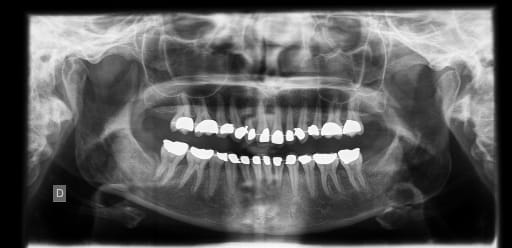

voilà la pano, alors je la tue ou je lui donne une chance?!

Pano x4bh6z - Eugenol

la 12 a soi-disant sa racine bien en place (j'ai vérifié sur la pano, c'est pas faux)

mais vue sa tronche, on dirait qu'elle est distalée...:-(

selon Madame l'orthodontiste c'est comme ça et pas autrement et faut envisager une améloplastie :-( (je la haie celle-là :-()

mais est-ce que y a pas moyen d'avoir des racines un peu moins parallèles et cette dent droite?!

Ainsi qu'il a été judicieusement remarqué, il semblerait y avoir une version de l'ensemble du secteur latéral.

Et on arrive au talon d'Achille de cette technique car pour corriger, it's very difficult. Dur...dur de repositionner, dur...dur de plier l'arc...c'est là ou on voit la dextérité et l'expérience du praticien.Et je ne parle que de modifier l'axe de 12 ( a voir sur la photo, le collet à l'air de traviol...donc la racine doit l'être aussi et pas seulement le bord occlusal).